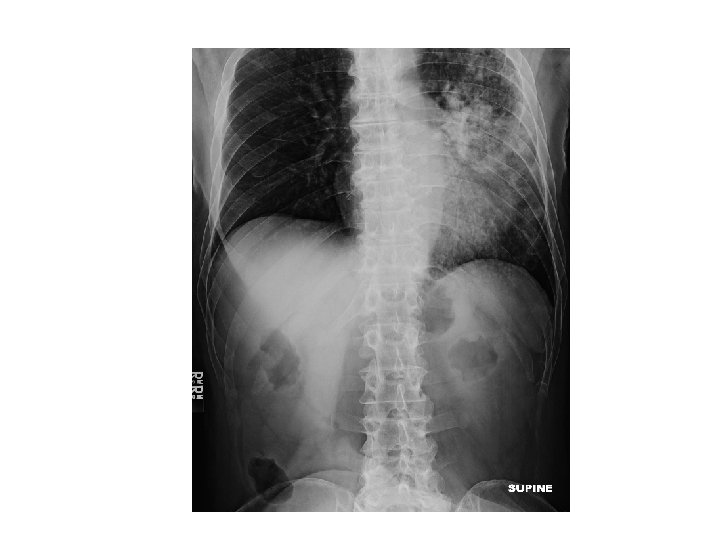

ER work-up • Abdominal XR = No obstruction/ air fluid level Atelectasis with central bronchial obstruction